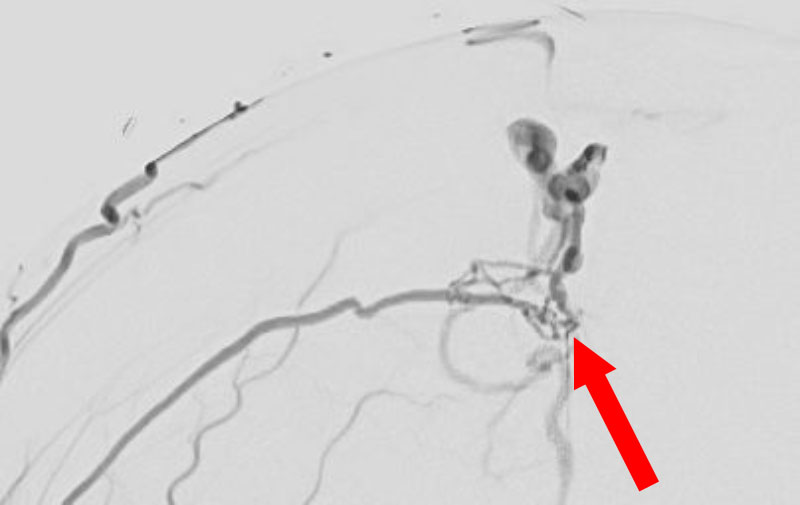

1615

'26年2月21日

硬膜動静脈瘻

50代

大阪府の病院

後

手術日